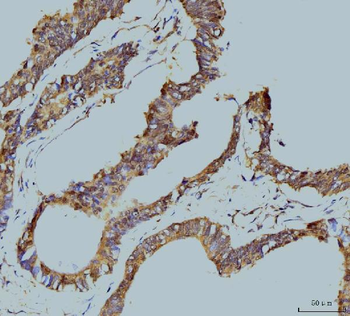

IHC analysis of TBP-1/PSMC3 using anti-TBP-1/PSMC3 antibody. TBP-1/PSMC3 was detected in paraffin-embedded section of human appendicitis tissue. Heat mediated antigen retrieval was performed in EDTA buffer (pH8.0, epitope retrieval solution). The tissue section was blocked with 10% goat serum. The tissue section was then incubated with 2 µg/ml rabbit anti-TBP-1/PSMC3 Antibody overnight at 4°C. Biotinylated goat anti-rabbit IgG was used as secondary antibody and incubated for 30 minutes at 37°C. The tissue section was developed using Strepavidin-Biotin-Complex (SABC) with DAB as the chromogen.